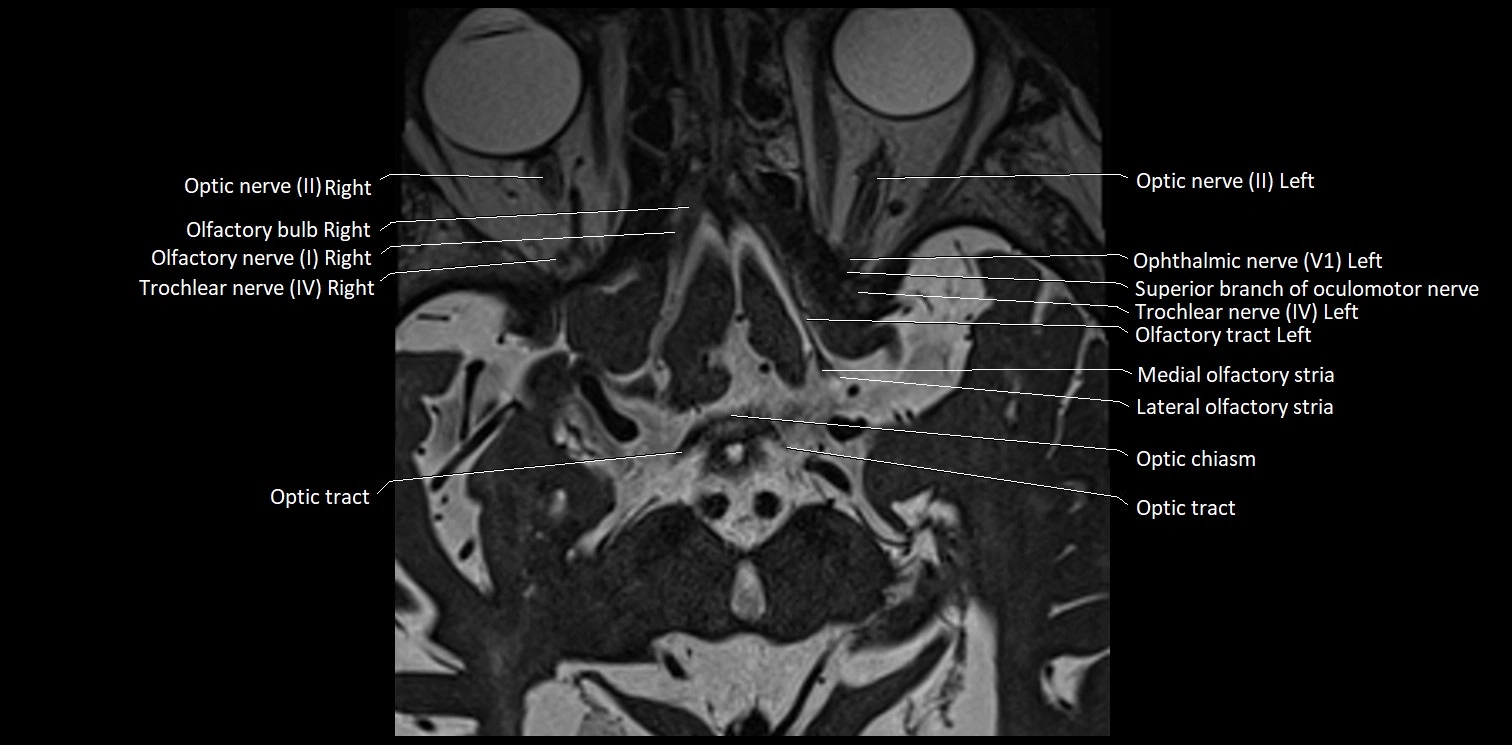

MRI Appearance

• The abducens nerve is a small, thin, linear structure

• Best visualized on high-resolution T2-weighted 3D MRI sequences (e.g., FIESTA or CISS)

• Seen as a hypointense (dark) line running from the brainstem at the pontomedullary junction, traversing the prepontine cistern, and entering Dorello’s canal under the petrosphenoidal ligament, then into the cavernous sinus, and finally the orbit

• May be challenging to visualize in standard MRI due to its small size

• Pathology may be inferred by absence, displacement, or enhancement of the nerve